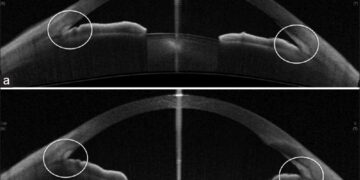

Σύμφωνα με το άρθρο με τίτλο “Bisphosphonate Use Linked to Increased Risk of Acute Angle Closure”, μια πρόσφατη μελέτη υποδεικνύει μια στατιστικά σημαντική συσχέτιση μεταξύ της χρήσης διφωσφονικών και του αυξημένου κινδύνου οξέος γλαυκώματος κλειστής γωνίας. Το οξύ γλαυκώμα κλειστής γωνίας είναι μια επείγουσα οφθαλμολογική κατάσταση που χαρακτηρίζεται από απότομη αύξηση της ενδοφθάλμιας πίεσης, η οποία μπορεί να οδηγήσει σε σοβαρή απώλεια όρασης εάν δεν αντιμετωπιστεί άμεσα.

Ο ακριβής μηχανισμός μέσω του οποίου τα διφωσφονικά μπορεί να αυξάνουν τον κίνδυνο οξέος γλαυκώματος κλειστής γωνίας δεν είναι πλήρως κατανοητός. Ωστόσο, υπάρχουν διάφορες θεωρίες. Μια πιθανή εξήγηση είναι ότι τα διφωσφονικά μπορεί να επηρεάζουν τη δομή ή τη λειτουργία του ακτινωτού σώματος του οφθαλμού, το οποίο είναι υπεύθυνο για την παραγωγή και την αποχέτευση του υδατοειδούς υγρού. Μια διαταραχή σε αυτή τη διαδικασία θα μπορούσε να οδηγήσει σε αύξηση της ενδοφθάλμιας πίεσης και, κατ’ επέκταση, σε οξύ γλαύκωμα κλειστής γωνίας.